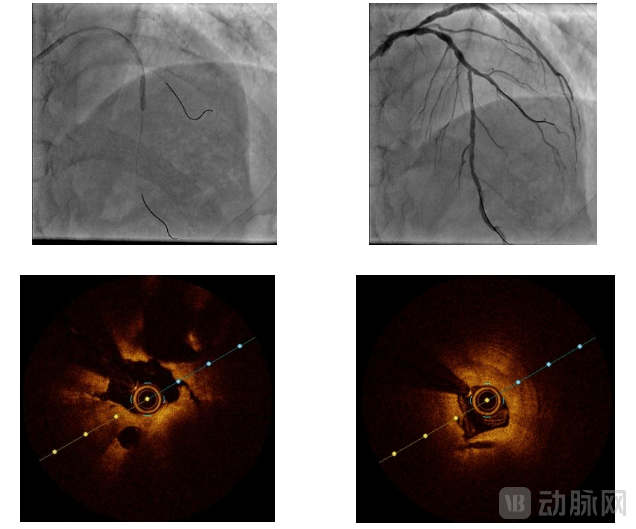

介入治疗靶病变为前降支中段,6F EBU3.5指引导管送至左冠口,将导丝分别送至前降支及第一对角支远段,于前降支送入OCT导管回撤行OCT检查可见脂质斑块,最小管腔面积为1.9mm²,遂决定进一步行前降支介入治疗。术中使用Scoreflex TRIO 2.5*15m球囊于病变处以8atm*10秒扩张,复查造影残余狭窄改善明显,残余狭窄小于30%,TIMI血流III级;于病变处植入支架一枚以10atm*10秒扩张释放,取非顺应性球囊于支架内16atm*10秒后扩张塑形,复查造影提示支架扩张满意,无残余狭窄,远端TIMI血流III级。

复查OCT提示前降支支架扩张满意,贴壁良好,支架膨胀率90%,手术成功。